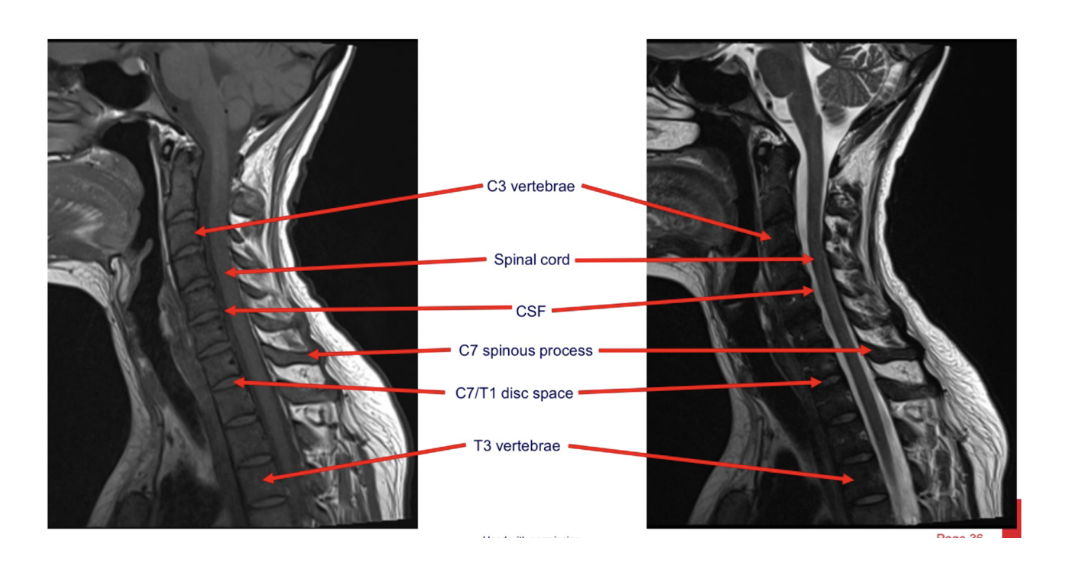

What are the sequences and what is the pathology?

• T1, STIR, T1FS C+